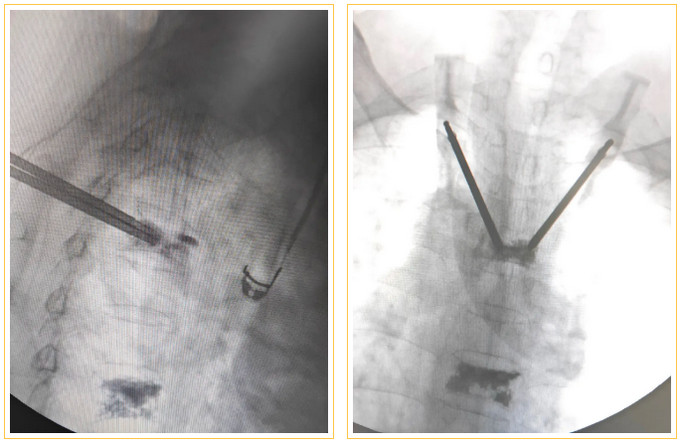

綜合陳阿姨骨折及骨質(zhì)疏松情況,保守治療需要長期絕對臥床,并發(fā)癥多,如肺炎,褥瘡,血栓,患者也難以堅(jiān)持。林翔主任醫(yī)師建議手術(shù)治療,并制定了微創(chuàng)手術(shù)方案:經(jīng)皮T4、T7椎體后凸成形術(shù)。

椎體成形術(shù)是一種脊柱微創(chuàng)手術(shù),適合于骨質(zhì)疏松性壓縮骨折的治療,皮膚切口僅2~3毫米,在X線透視引導(dǎo)下,通過穿刺針向骨折的椎體內(nèi)注入“骨水泥”(一種骨科醫(yī)用材料,由于它在凝固固化后外觀和物理特性像建筑、裝修用的白水泥而得名)將骨折的骨頭粘合在一起,重建脊柱穩(wěn)定性,達(dá)到緩解疼痛的目的,使患者早期恢復(fù)正?;顒?。

術(shù)中在細(xì)小的通道中穿刺打入骨水泥

面對如此高難度、高風(fēng)險(xiǎn)的手術(shù),有著30多年骨科臨床工作經(jīng)驗(yàn)的王榮茂、林翔主任醫(yī)師,在做足了充分的術(shù)前準(zhǔn)備后,帶領(lǐng)團(tuán)隊(duì)劉蔚楠、林家鐘博士等迎難而上。他與手術(shù)室、麻醉科密切配合,在陳磊麻醉醫(yī)師干脆利落的麻醉下,僅用時(shí)20分鐘就順利為陳阿姨完成手術(shù)。